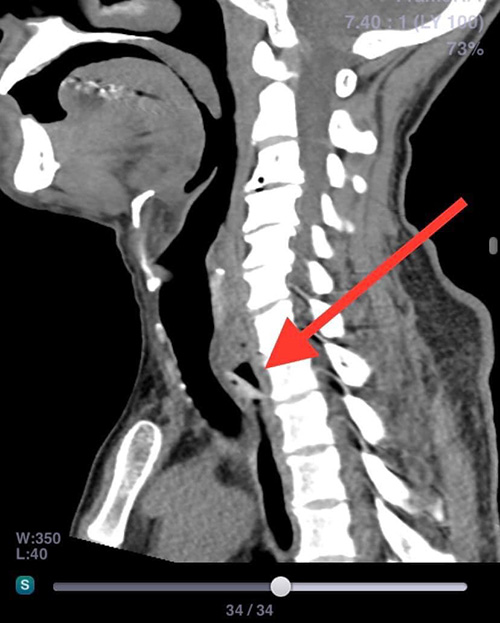

จากนั้นจึงเรียกภรรยาและลูก ๆ มาช่วยกัน จนภรรยาของตนถามว่า ฟันปลอมหายไปไหน จึงทำให้รู้ทันทีว่าสิ่งแปลกปลอมที่หลุดไปติดลำคอก็คือฟันปลอม ด้วยความตกใจจึงรีบขับรถด้วยตนเองไปยังโรงพยาบาลที่อยู่ใกล้เคียงเพื่อให้แพทย์ช่วยเหลือเอาฟันปลอมที่หลุดติดคอออกโดยเร็ว หลังจากแพทย์มีการเอกซเรย์และทำซีทีสแกนอย่างละเอียด แล้วก็พบว่ามีฟันปลอมหลุดไปติดที่หลอดอาหาร โชคดีที่ไม่หลุดไปติดที่หลอดลม จึงมีการระดมแพทย์ทั้งศัลยกรรมและแพทย์หู คอ จมูก จำนวน 5 คน มาช่วยกันทำการส่องกล้องดึงเอาฟันปลอมออกจากคอได้อย่างปลอดภัย จึงอยากฝากเตือนไปยังผู้ใช้ฟันปลอมทุกคนว่าควรมีการตรวจสอบตลอด ถ้าหากมีอาการหลวมก็ขอให้ไปพบทันตแพทย์ทำใหม่ อย่าประมาท

หมอจึงส่งเอกซเรย์คอมพิวเตอร์ จึงพบว่ามีฟันเทียมติดค้างในลำคอจริง

พอรู้ตำแหน่งแน่นอนจึงนำคนไข้เข้าห้องผ่าตัดและใช้กล้องสอดไปคีบฟันเทียมออกมาได้สำเร็จ